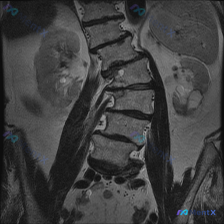

整理到一份腰椎MRI T1加权像冠状位的影像分析资料,先不说最终倾向,把核心发现放出来大家讨论下:

核心影像表现:

- 脊柱:明显腰椎右侧凸畸形,椎体边缘骨质增生、部分模糊,椎间隙左右不对称、部分狭窄,椎间盘T1信号广泛减低;小关节间隙窄、关节突肥大,凹侧结构紊乱。

- 骨髓信号:关键! 椎体骨髓信号不均匀,T1像上可见散在、多发的局灶性低信号区(暗灰色斑点/斑块),分布在多个椎体,未见完全均匀一致的脂肪信号。

- 其他:椎间孔形态改变(凹侧可能狭窄),双侧腰大肌/竖脊肌不对称,双肾、部分骶髂关节未见明显异常。

第一眼只看“脊柱侧弯”可能会归为退行性变,但这份资料里最值得讨论的其实是骨髓信号的问题。

📋答案:基于影像征象的综合诊断排序:1. 多发性骨髓瘤或浆细胞骨髓浸润(最需优先排除的致命性风险);2. 退行性脊柱侧弯合并Modic I型改变;3. 实体肿瘤骨转移;4. 单纯退行性改变伴骨髓脂肪坏死/纤维化(仅作为排除后的备选)。